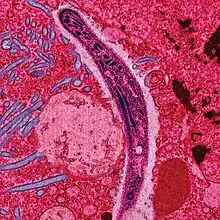

Le Plasmodium se présente sous la forme d'un protozoaire très petit (1 à 2 µm selon les formes). La coloration au May-Grünwald-Giemsa montre qu'il est constitué d'un cytoplasme bleu pâle entourant une vacuole nutritive claire et contenant un noyau rouge et du pigment brun-doré ou noir (hémozoïne).

Au début de la longue phase sanguine[140] : les mérozoïtes s'accolent aux globules rouges, les envahissent, s'y développent en trophozoïtes puis s'y divisent (schizontes).

En se diffusant, les mérozoïtes font éclater les globules rouges (c'est l'hémolyse).

Les manifestations cliniques du paludisme apparaissent au début de la phase sanguine, lorsque la parasitémie dépasse un seuil, variable selon les individus[142]. Cette multiplication asexuée des plasmodiums à l'intérieur des hématies fait du paludisme, au sens propre, une maladie parasitaire des globules rouges.

La lyse des hématies parasitées (éclatement des schizontes mûrs ou rosaces) libère de nouveaux parasites (mérozoïtes) qui contaminent à leur tour d'autres hématies. Cette destruction entraine aussi une libération des déchets du métabolisme plasmodial (pigments et débris cellulaires du globule rouge, ou hémozoïne), ces substances pyrogènes perturbent le fonctionnement de l'hypothalamus (production de cytokine comme le TNFα) et causent de fortes fièvres[143].